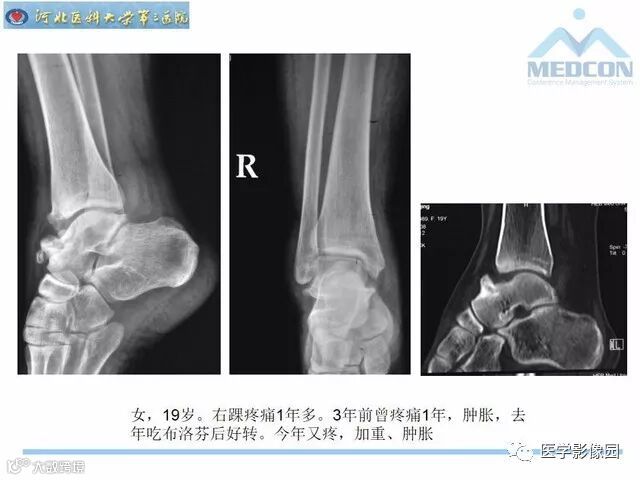

踝关节撞击综合征影像诊断,干货满满,值得收藏!

导读:踝关节撞击综合征影像诊断。干货满满,值得收藏!

踝关节撞击综合征影像诊断。干货满满,值得收藏!